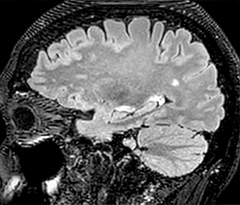

Fast MS protocol with optional sequences

The abbreviated MS protocol for brain is only around 9 minutes, so in case of suspected multiple sclerosis, one or two more advanced sequences may be added, such as PSIR (phase sensitive inversion recovery) or susceptibility-weighted sequences to help us make more confident diagnoses in these inflammatory cases.

In this example, the optional 3D multishot susceptibility weighted sequence with 0.6 mm isotropic voxels is 2 lesions with a central vein sign (arrows) and one lesion with a phase-rim sign (arrowhead). The total scan time, including SmartBrain and axial PD/T2 3mm, is 11:10 min. and is 18:30 min. with the optional 3D PSIR and 3D SWI multishot included.

3D TFE T1

3D FLAIR

DWI image

3D T1w TSE Gd

3D PSIR

3D SWI